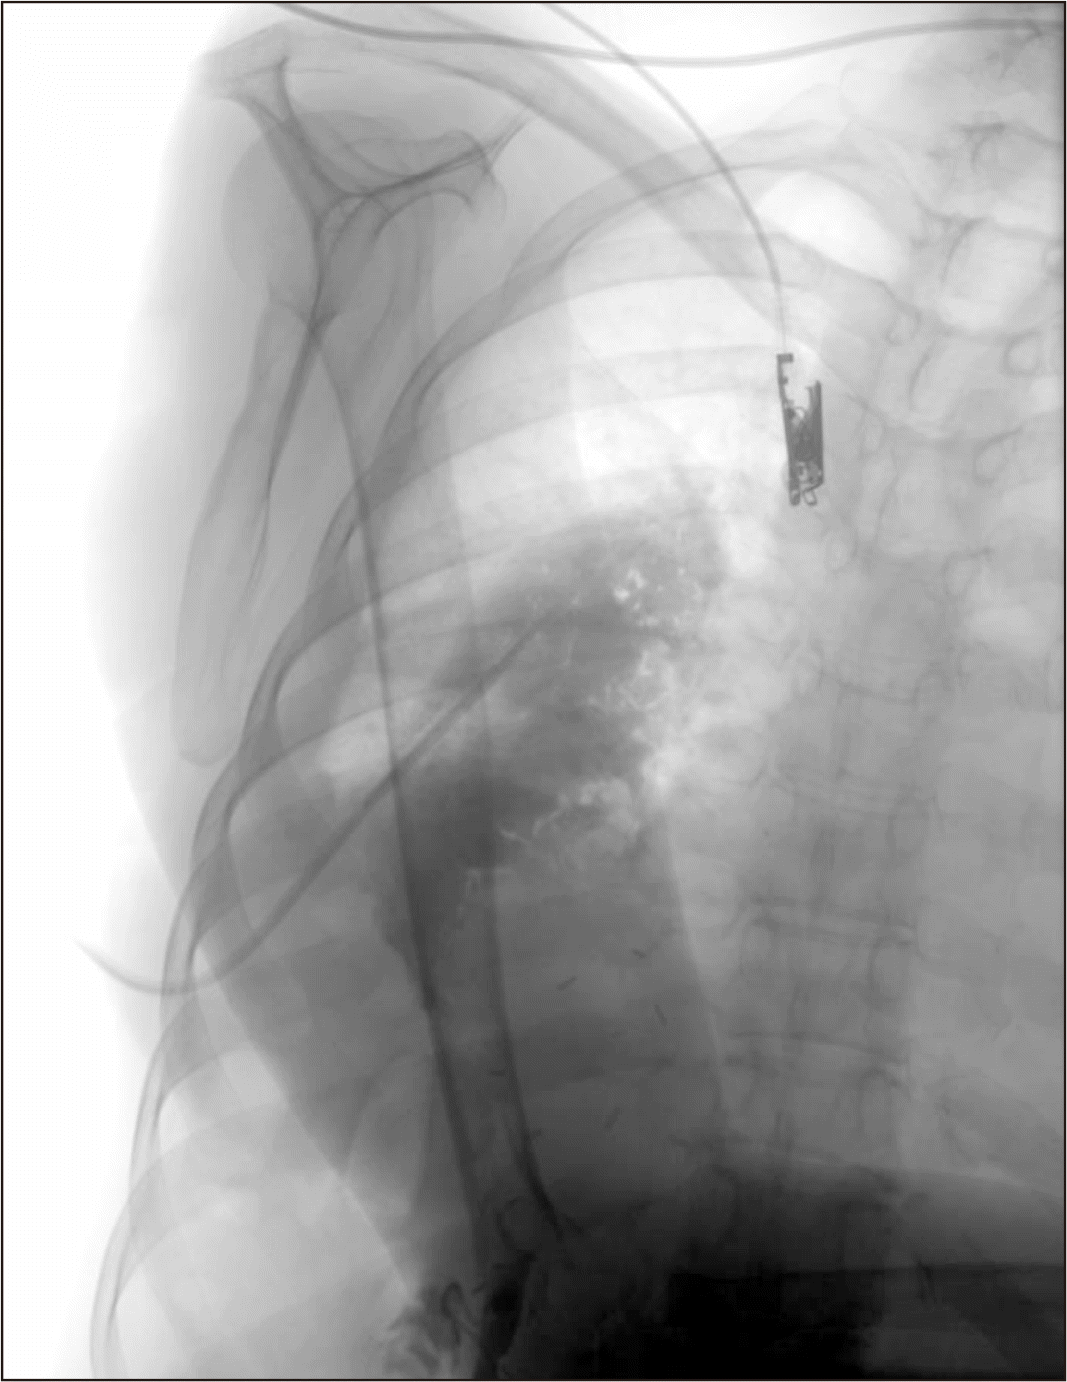

Chest X-ray after pigtail insertion; the pleural biloma is visible. (A) Chest X-Ray after pigtail insertion. (B) Chest X-ray just before pigtail insertion.

Fig. 4

Chest X-ray of the right pleural cavity with a pigtail drain inserted into the biloma in the right pleural cavity.